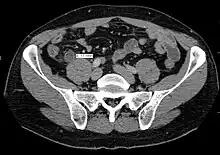

Computed tomography

Where it is readily available, computed tomography (CT) has become frequently used, especially in people whose diagnosis is not obvious on history and physical examination. Although some concerns about interpretation are identified, a 2019 Cochrane review found that sensitivity and specificity of CT for the diagnosis of acute appendicitis in adults was high.[61] Concerns about radiation tend to limit use of CT in pregnant women and children, especially with the increasingly widespread usage of MRI.[62][63]

The accurate diagnosis of appendicitis is multi-tiered, with the size of the appendix having the strongest positive predictive value, while indirect features can either increase or decrease sensitivity and specificity. A size of over 6 mm is both 95% sensitive and specific for appendicitis.[64]

However, because the appendix can be filled with fecal material, causing intraluminal distention, this criterion has shown limited utility in more recent meta-analyses.[65] This is as opposed to ultrasound, in which the wall of the appendix can be more easily distinguished from intraluminal feces. In such scenarios, ancillary features such as increased wall enhancement as compared to adjacent bowel and inflammation of the surrounding fat, or fat stranding, can be supportive of the diagnosis. However, their absence does not preclude it. In severe cases with perforation, an adjacent phlegmon or abscess can be seen. Dense fluid layering in the pelvis can also result, related to either pus or enteric spillage. When patients are thin or younger, the relative absence of fat can make the appendix and surrounding fat stranding difficult to see.[65]